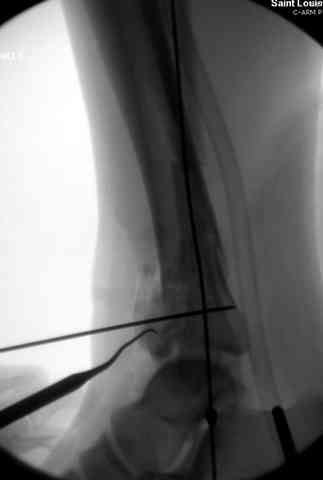

Добавлены КТ снимки. Прошу прощения за качество.

С уважением, Коваленко А.Н.

Снова приветствую вас, коллеги. К моменту вступления в обсуждение аксакалов, операция была, увы, выполнена(31.10.07.) Начали с доступа к наружной лодыжке, произвели ее фиксацию спицами, развернули кусок заднего края, наложили дистрактор, затем произвели дистракцию, фиксацию спицами дистального эпиметафиза б/бк,Рентгено-контроль. синтез наружной лодыжки 1/3пластиной. из двух коротких разрезов сформирован канал под медиальную тибиальную пластину LCP. Края ран ушиты без натяжения. Прочувствовать жесткость фиксации винтами с угловой стабильностью не удалось, поэтому дистрактор оставлен на энное время.

На представленных R-снимках не окончательный вид после остеосинтеза. Дистальная опора давила на стопу, пришлось ее сместить проксимально, в рез-те чего, она закрыла щель сустава, последние снимки не информативны.